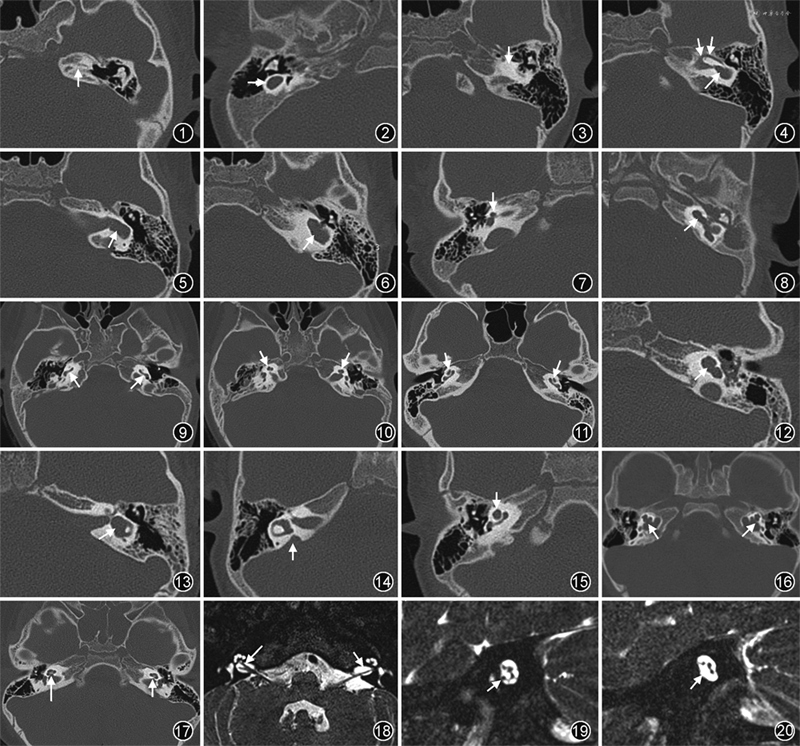

1.迷路未发育(complete labyrinthine aplasia,CLA):也称为Michel畸形,影像表现为内耳结构完全缺失,但骨迷路包囊之密质骨可以存在,可伴有颞部岩部发育不良。CLA可分为3个亚型:CLA伴岩锥发育不良或未发育(图1)、CLA不伴骨迷路包囊、CLA伴骨迷路包囊。

2.初始听泡:内耳表现为数毫米的小囊状,无内听道(图2),可以存在部分半规管结构。

3.耳蜗未发育:表现为耳蜗缺失(图3),可分为伴正常前庭半规管和伴前庭扩大(图4)两个亚型。后者需与共同腔畸形相鉴别,但有时很难区分。

4.共同腔畸形:前庭和耳蜗呈单一或融合腔,内听道通常进入其中部,可伴有部分发育的半规管(图5,6)。

5.耳蜗发育不全(cochlear hypoplasia,CH):耳蜗可以与前庭相区分,且耳蜗的尺寸小于正常,占内耳畸形的15%~23%[7]。CH影像表现多样,也常伴有前庭半规管畸形、蜗神经孔及内听道异常等。CH可分为4型:CH-Ⅰ,芽状耳蜗(图7);CH-Ⅱ,囊性耳蜗发育不全(图8);CH-Ⅲ,耳蜗圈数少于2圈(图9,10);CH-Ⅳ,耳蜗尖中旋发育不全(图11)。耳蜗宽度和高度的测量有助于提高诊断CH的敏感性[4]。

6.不完全分隔(incomplete partitian,IP):可分为3个亚型。IP-Ⅰ,约占内耳畸形的20%,又称为囊性耳蜗前庭畸形,耳蜗呈囊性外观,蜗轴及耳蜗分隔完全缺失,常伴有扩张的前庭,但耳蜗和前庭可以相区分,耳蜗的大小与正常相仿(图12,13)。IP-Ⅱ,即经典Mondini畸形,是最常见的耳蜗畸形,包括3个典型征象:蜗轴尖部缺陷,导致耳蜗尖中旋融合呈囊样;前庭轻度扩大;前庭导水管扩大(图14,15)。IP-Ⅲ,占内耳畸形的0.9%~2.0%,其特征表现为内听道球样扩张、蜗轴完全缺失,但耳蜗分旋存在(图16),可累及整个骨迷路包囊,包括前庭、半规管、前庭窗等[8]。

7.大前庭导水管(enlarged vestibular aqueduct,EVA):仅表现为前庭导水管扩大,而耳蜗、前庭半规管正常。诊断EVA的传统标准(Valvassori标准)为前庭导水管中点处宽度>1.5 mm;也有学者推荐采用Cincinnati标准,即前庭导水管中点处≥1 mm或后部开口处≥2 mm[9, 10]。

8.前庭半规管畸形:可表现为前庭扩大、半规管短小、狭窄、增宽,以及半规管缺失等。单独的前庭或半规管畸形很常见,其他内耳畸形也常伴有不同程度的前庭半规管畸形。

9.蜗神经孔异常:正常蜗神经孔的宽度为1.4~2.5 mm,其宽度<1.4 mm可考虑为蜗神经孔狭窄,也可表现为蜗神经孔闭锁(图17),可伴有或不伴有内听道狭窄。

10.前庭蜗神经异常:通常,HRCT可以对内耳畸形进行正确的诊断和分类,但完整的评估应包括MRI对于前庭蜗神经的评估,尤其是对蜗神经的评估,可表现为神经发育不良或缺失(图18~20)。在单侧重度及极重度感音神经性聋的儿童患者中,蜗神经发育不良或缺失的发生率可达48%[11]。